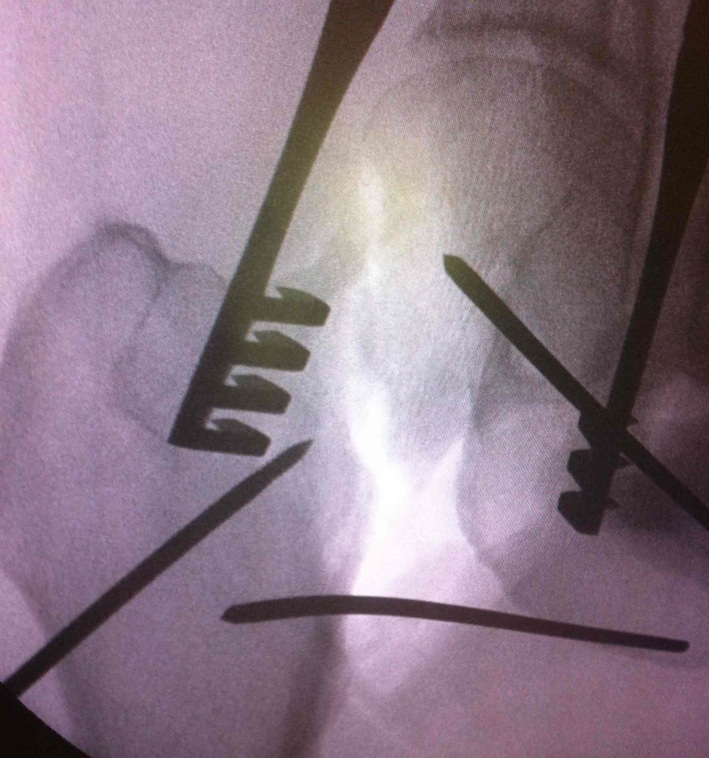

Smith Petersen anterior approach, with capsulotomy and reduction with pins

Reduction techniques

Obtain anatomical reduction under direct vision

- Steinman pin in femoral head

- second Steinman pin in femur to correct external rotation force

Check reduction on image intensifier

- ensure no varus on AP

- obtain lateral by adducting and IR hip / ensure good reduction on lateral